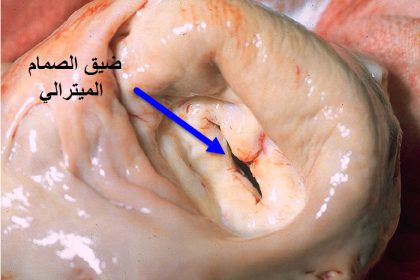

4 Articlesأمراض صمامات القلب